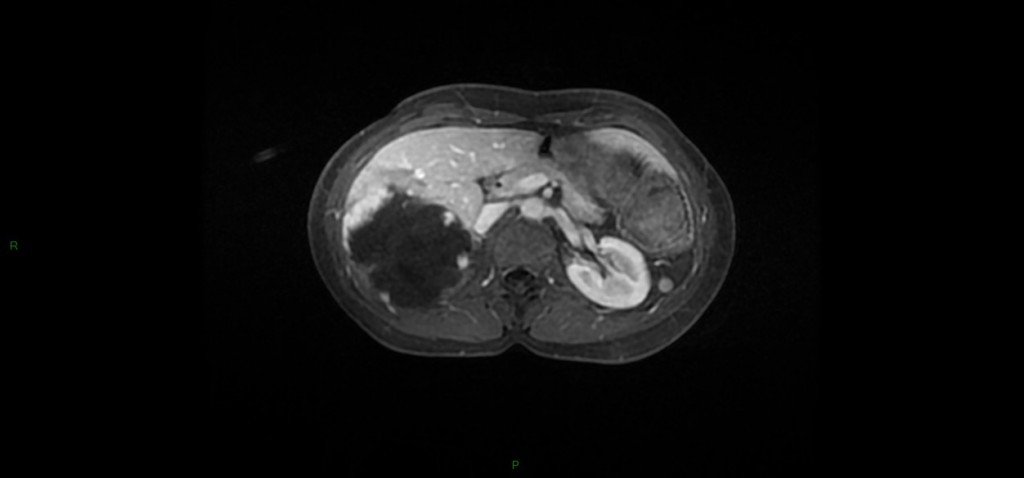

Tumeurs hépatiques – Angiome hépatique Alexandre Ladoux il y a 11 ans ANGIOME CAVERNEUX A reconnaître +++ Unique 90% 80% < 4cm Franc hT1, HT2 liquidien, contours polylobés, disparait en bili-IRM Prise de contraste en mottes discontinues, précoce, avec remplissage centripète (lacs veineux) progressif jusque complet (tardif+++) Possible portion liquidienne centrale : dégenerescence mucoïde ANGIOME CAPILLAIRE (hémangiome) Pdc intense équivalent à l’aorte à tous les temps Diagnostic en échographie : si 4 critères présents Hyperechogène homogène, sans signal Doppler couleur +- renforcement postérieur < 3cm Bilan hépatique normal En dehors de contexte néoplasique DDx : lésions fibreuses avec remplissage centripète: Cholangiocarcinome fibro-lamellaire : Pdc périph mais CONTINUE Métastase d’ADK colique mucineux (HT2 liquidien) ou neuroendocrine : Pdc tardive périph CONTINUE jamais complète Exemples d’angiomes hépatiques Angiome géant Angiomes et adénome graisseux Partager : Partager sur Facebook(ouvre dans une nouvelle fenêtre) Facebook Partager sur LinkedIn(ouvre dans une nouvelle fenêtre) LinkedIn Partager sur X(ouvre dans une nouvelle fenêtre) X Partager sur WhatsApp(ouvre dans une nouvelle fenêtre) WhatsApp Envoyer un lien par e-mail à un ami(ouvre dans une nouvelle fenêtre) E-mail Imprimer(ouvre dans une nouvelle fenêtre) Imprimer Plus Partager sur Tumblr(ouvre dans une nouvelle fenêtre) Tumblr Partager sur Pinterest(ouvre dans une nouvelle fenêtre) Pinterest